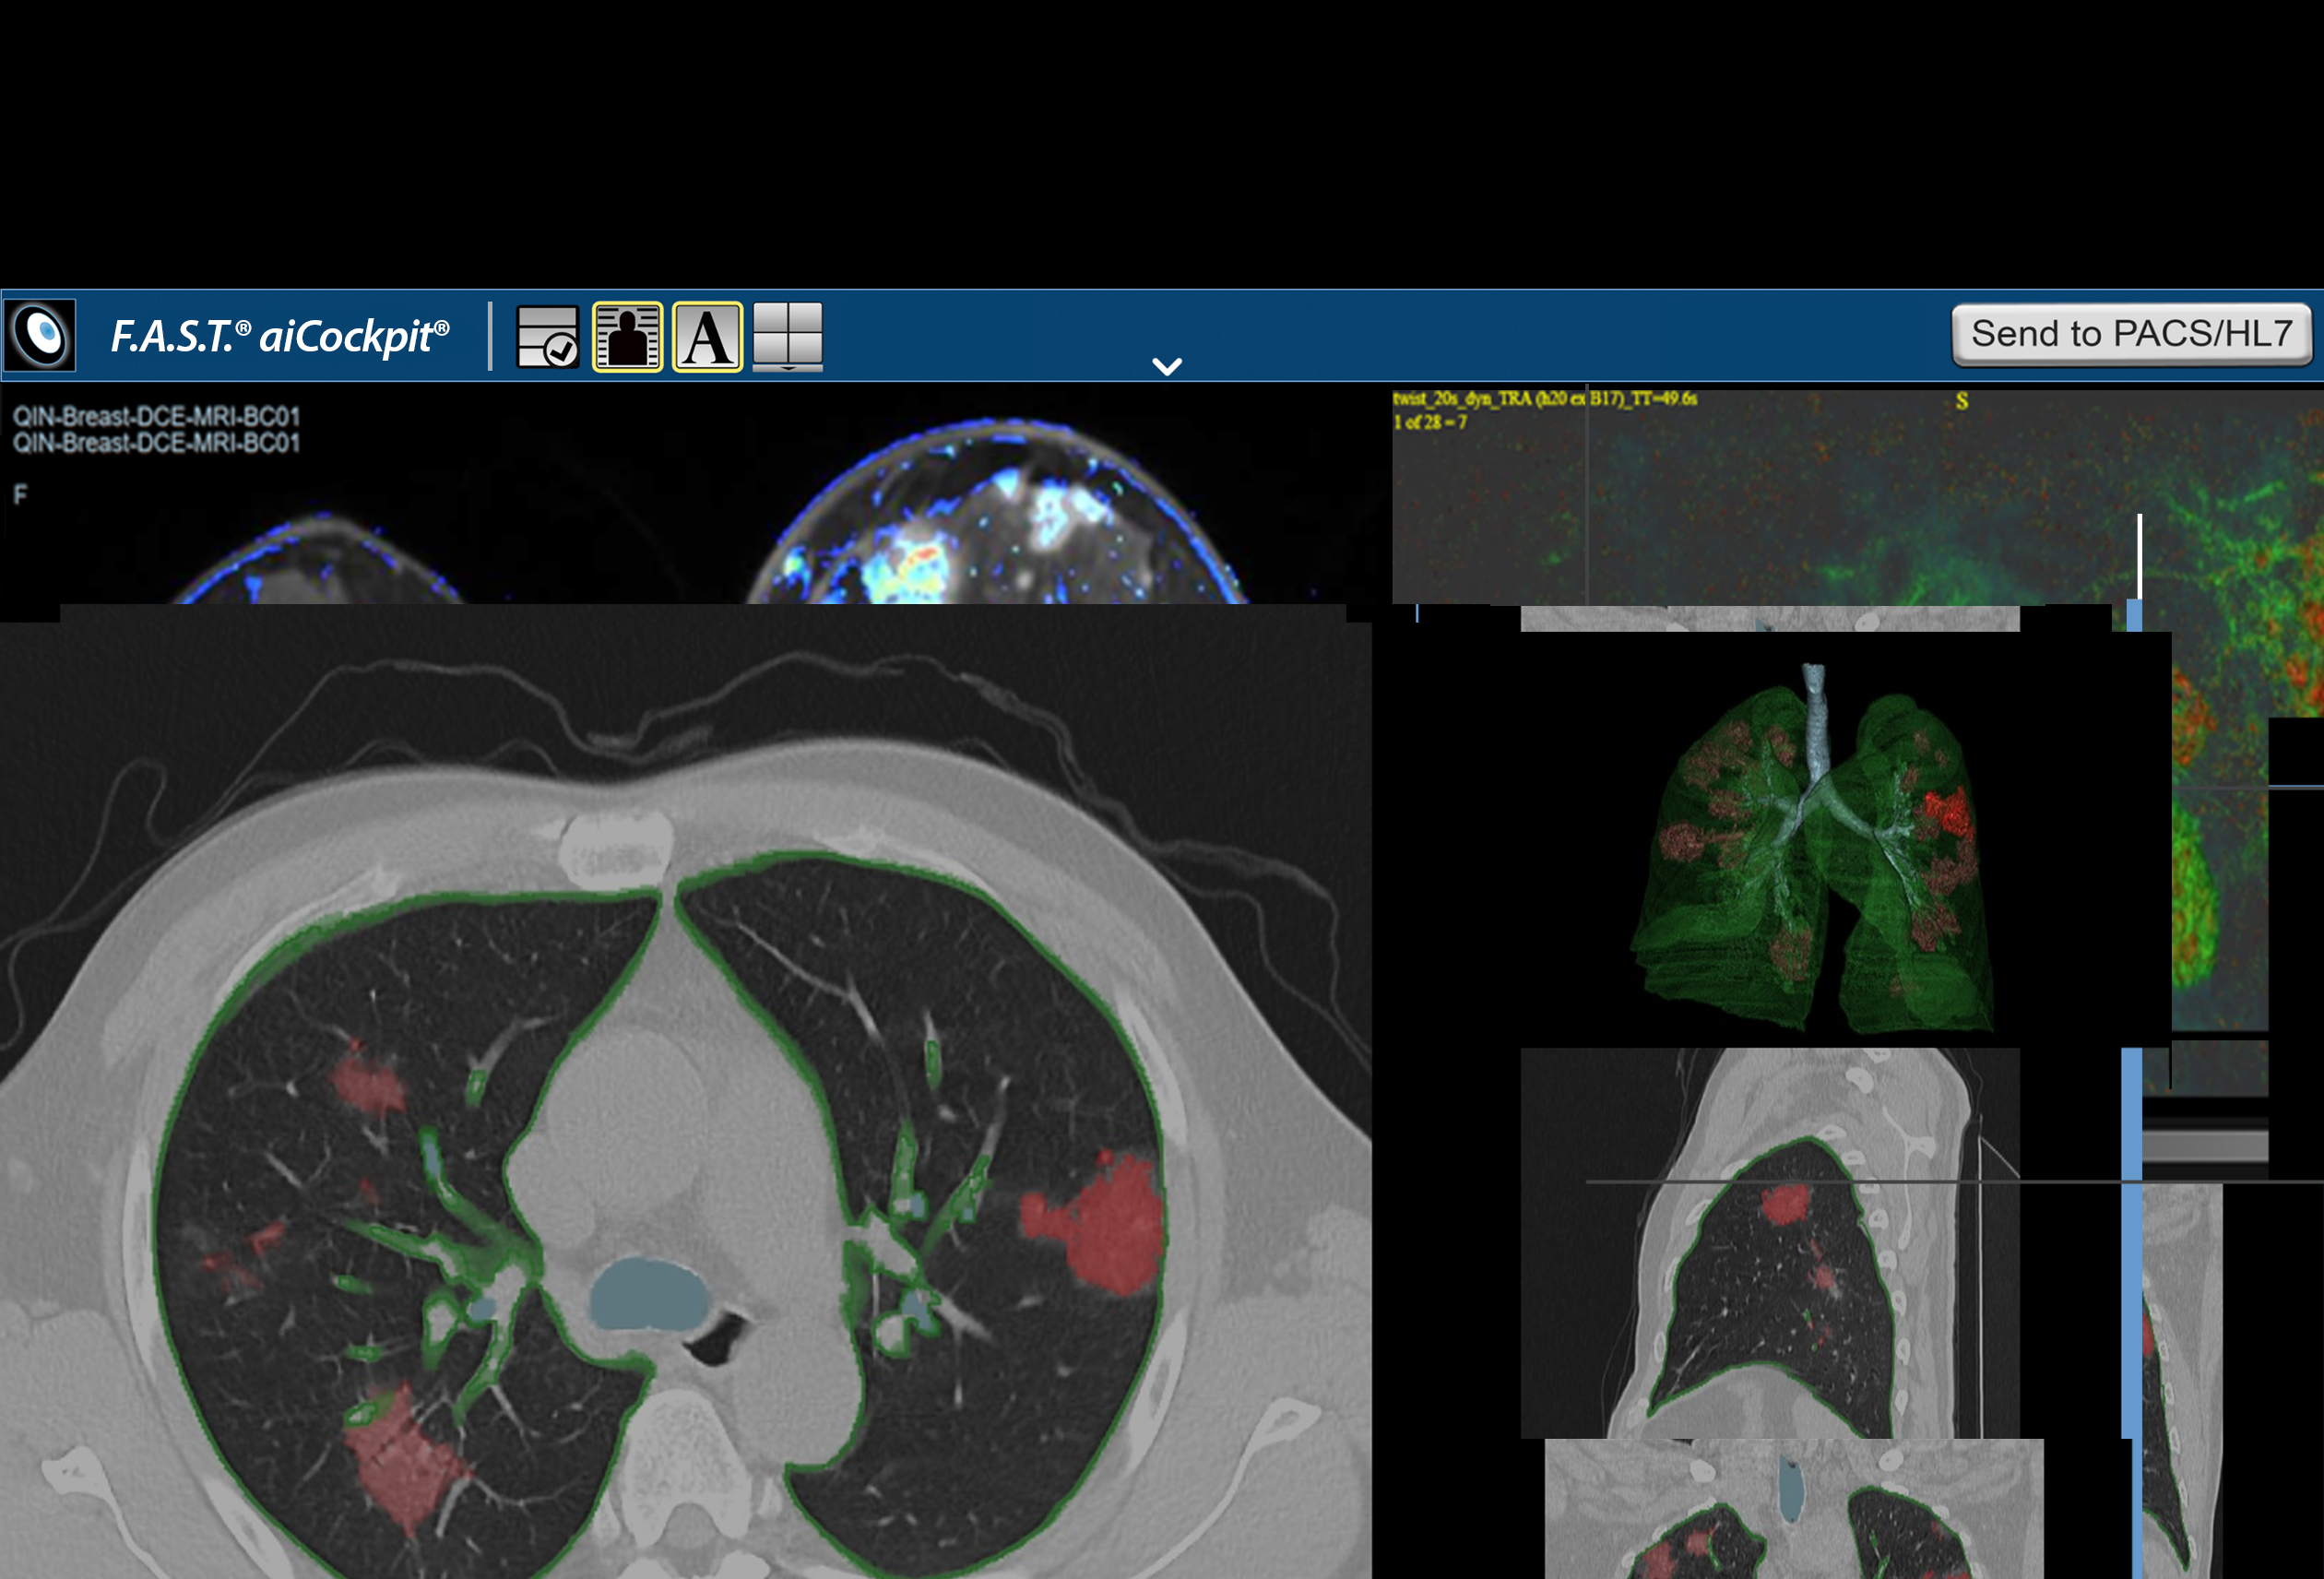

F.A.S.T. Pulmonary Workflow

F.A.S.T. Multiparametric MRI Workflow

F.A.S.T. AI Workflows

F.A.S.T. Pulmonary Workflow

F.A.S.T. Multiparametric MRI Workflow

F.A.S.T. AI Workflows